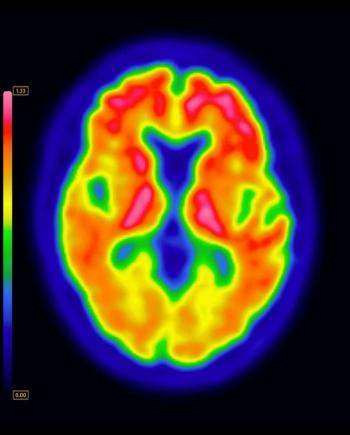

For patients with amyloid β (Aβ)-positive findings on positron emission tomography, higher educational attainment was associated with accelerated accumulation and spread of tau, according to new research.

For people with mild cognitive impairment (MCI), new research suggests that a combination of amyloid-positive and tau-positive PET findings is linked to a nearly 70 percent risk of progressing to dementia in five years in comparison to an approximate 30 percent risk for those with amyloid β positive and tau-negative PET.